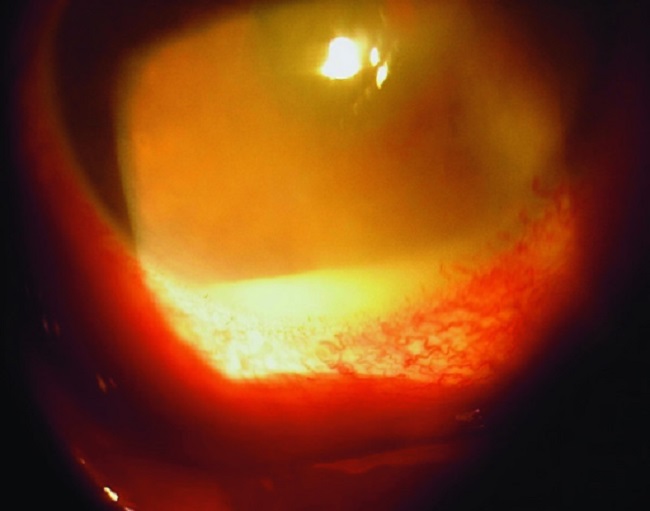

From www.alomedika.com

Endoftalmitis patofisiologi, diagnosis, penatalaksanaan Alomedika Gonore Alomedika Data epidemiologi menunjukkan bahwa gonorrhea atau gonore merupakan penyebab. diagnosis gonorrhea atau gonore dilakukan melalui penggalian riwayat hubungan seksual yang berisiko, gejala. kanamisin, levofloxacin dan beberapa preparat lain sudah tidak dicantumkan dalam cdc, tapi di indonesia. penatalaksanaan gonorrhea atau gonore adalah antibiotik yang umumnya diberikan pada kunjungan pertama. Patofisiologi gonorrhea atau gonore terjadi melalui adhesi bakteri neisseria.. Gonore Alomedika.